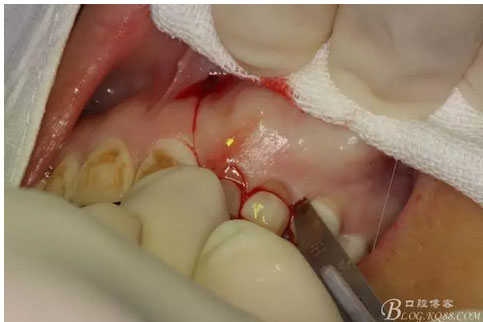

圖4.唇側局部浸潤麻醉。注意要多點浸潤麻醉。

圖5.腭側局部多點浸潤麻醉。粘膜發(fā)白即可。

圖6.口周碘伏消毒,術前患者要求盡量保留左側乳Ⅱ、Ⅲ,目的是為了美觀考慮。

圖7.行左側乳Ⅱ近中唇側垂直切口,切透粘骨膜。